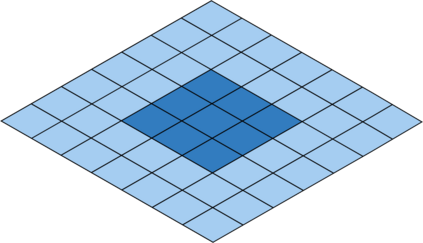

Deep Convolutional Neural Networks (DCNNs) are used extensively in biomedical image segmentation. However, current DCNNs usually use down sampling layers for increasing the receptive field and gaining abstract semantic information. These down sampling layers decrease the spatial dimension of feature maps, which can be detrimental to semantic image segmentation. Atrous convolution is an alternative for the down sampling layer. It increases the receptive field whilst maintains the spatial dimension of feature maps. In this paper, a method for effective atrous rate setting is proposed to achieve the largest and fully-covered receptive field with a minimum number of atrous convolutional layers. Furthermore, different atrous blocks, shortcut connections and normalization methods are explored to select the optimal network structure setting. These lead to a new and full-scale DCNN - Atrous Convolutional Neural Network (ACNN), which incorporates cascaded atrous II-blocks, residual learning and Fine Group Normalization (FGN). Application results of the proposed ACNN to Magnetic Resonance Imaging (MRI) and Computed Tomography (CT) image segmentation demonstrate that the proposed ACNN can achieve comparable segmentation Dice Similarity Coefficients (DSCs) to U-Net, optimized U-Net and hybrid network, but with significantly reduced trainable parameters due to the use of full-scale feature maps and therefore computationally is much more efficient for both the training and inference.